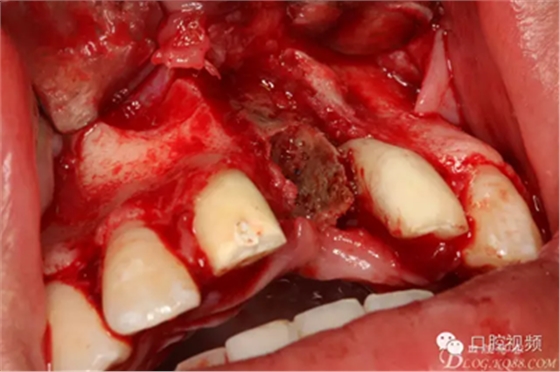

圖10.摘除死骨、并刮除周圍炎性肉芽組織。

圖11.球鉆修整牙槽骨面。

圖12.繼續(xù)清理創(chuàng)面周圍炎性組織